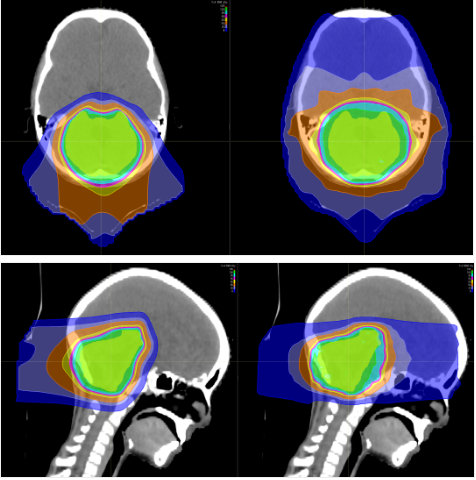

上图为髓母细胞瘤对全脑全脊髓照射剂量的分布图比较,传统放疗会对身体造成大范围的损害,波及脊柱周边的脏器,而质子治疗剂量分布图,脊髓周边的照射剂量机乎为零,不会造成损害及副作用。